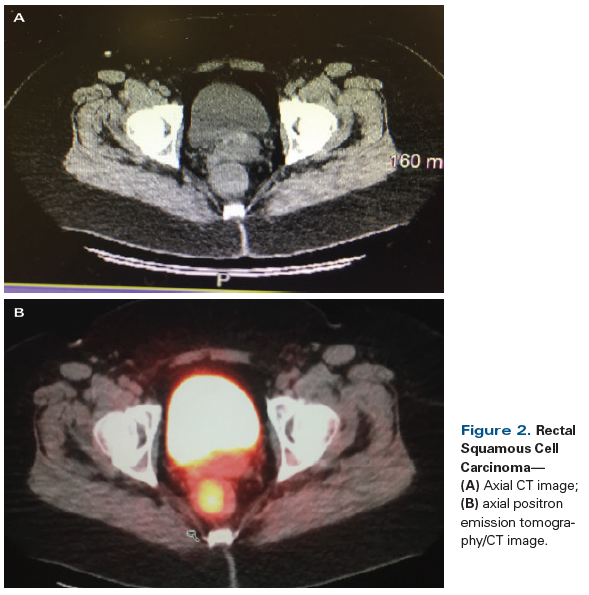

Figure 2. Rectal Squamous Cell Carcinoma

A 56-year-old Caucasian woman presented to her primary care physician with a 3-month history of intermittent bright red rectal blood with defecation. At her initial visit, a digital rectal examination, anoscopy, and a pelvic examination with DNA testing for high-risk human papillomavirus (HPV) were performed; all results were negative. She was referred for a colonoscopy, which revealed an abnormal area with a 3 × 4–cm mass in the rectum at a distance of 10 cm from the anal verge. Colonoscopic biopsy of this mass was consistent with invasive squamous cell carcinoma (Figures 1A and 1B); p16 immunohistochemistry staining of the biopsy specimen was positive (Figure 1C). Staging workup with a total body CT scan (Figure 2A) and positron emission tomography (PET)/CT scan (Figure 2B) confirmed the presence of a rectal mass, which demonstrated a standardized uptake value of 10. There was no evidence of nodal or distant metastasis. The patient was referred to medical oncology for further treatment recommendations.